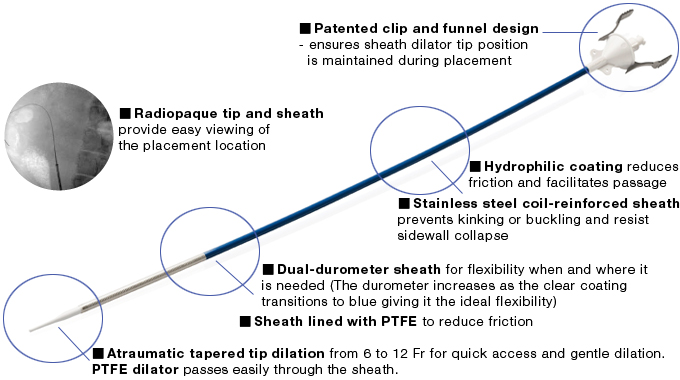

The patented UroPass Ureteral Access Sheath incorporates a number of innovative design features to meet this need and improve patient outcomes. With its patented dual durometer, hydrophilic coated outer sheath, and lubricious, tapered dilator, the UroPass glides easily through the urethra into the ureteral orifice to establish a superb conduit for atraumatic passage of endoscopes and retrieval devices.

Innovative design that offers twice secure engagement of the dilating catheter to outer acess sheath, enables safe and secure placement.

Patented one handed snap-in locking/release mechanism quickly releases the dilator when the sheath is in position.